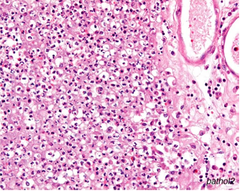

Describe Fat necrosis

a) enzymatic- acute pancreatitis & calcium saponification b) traumatic